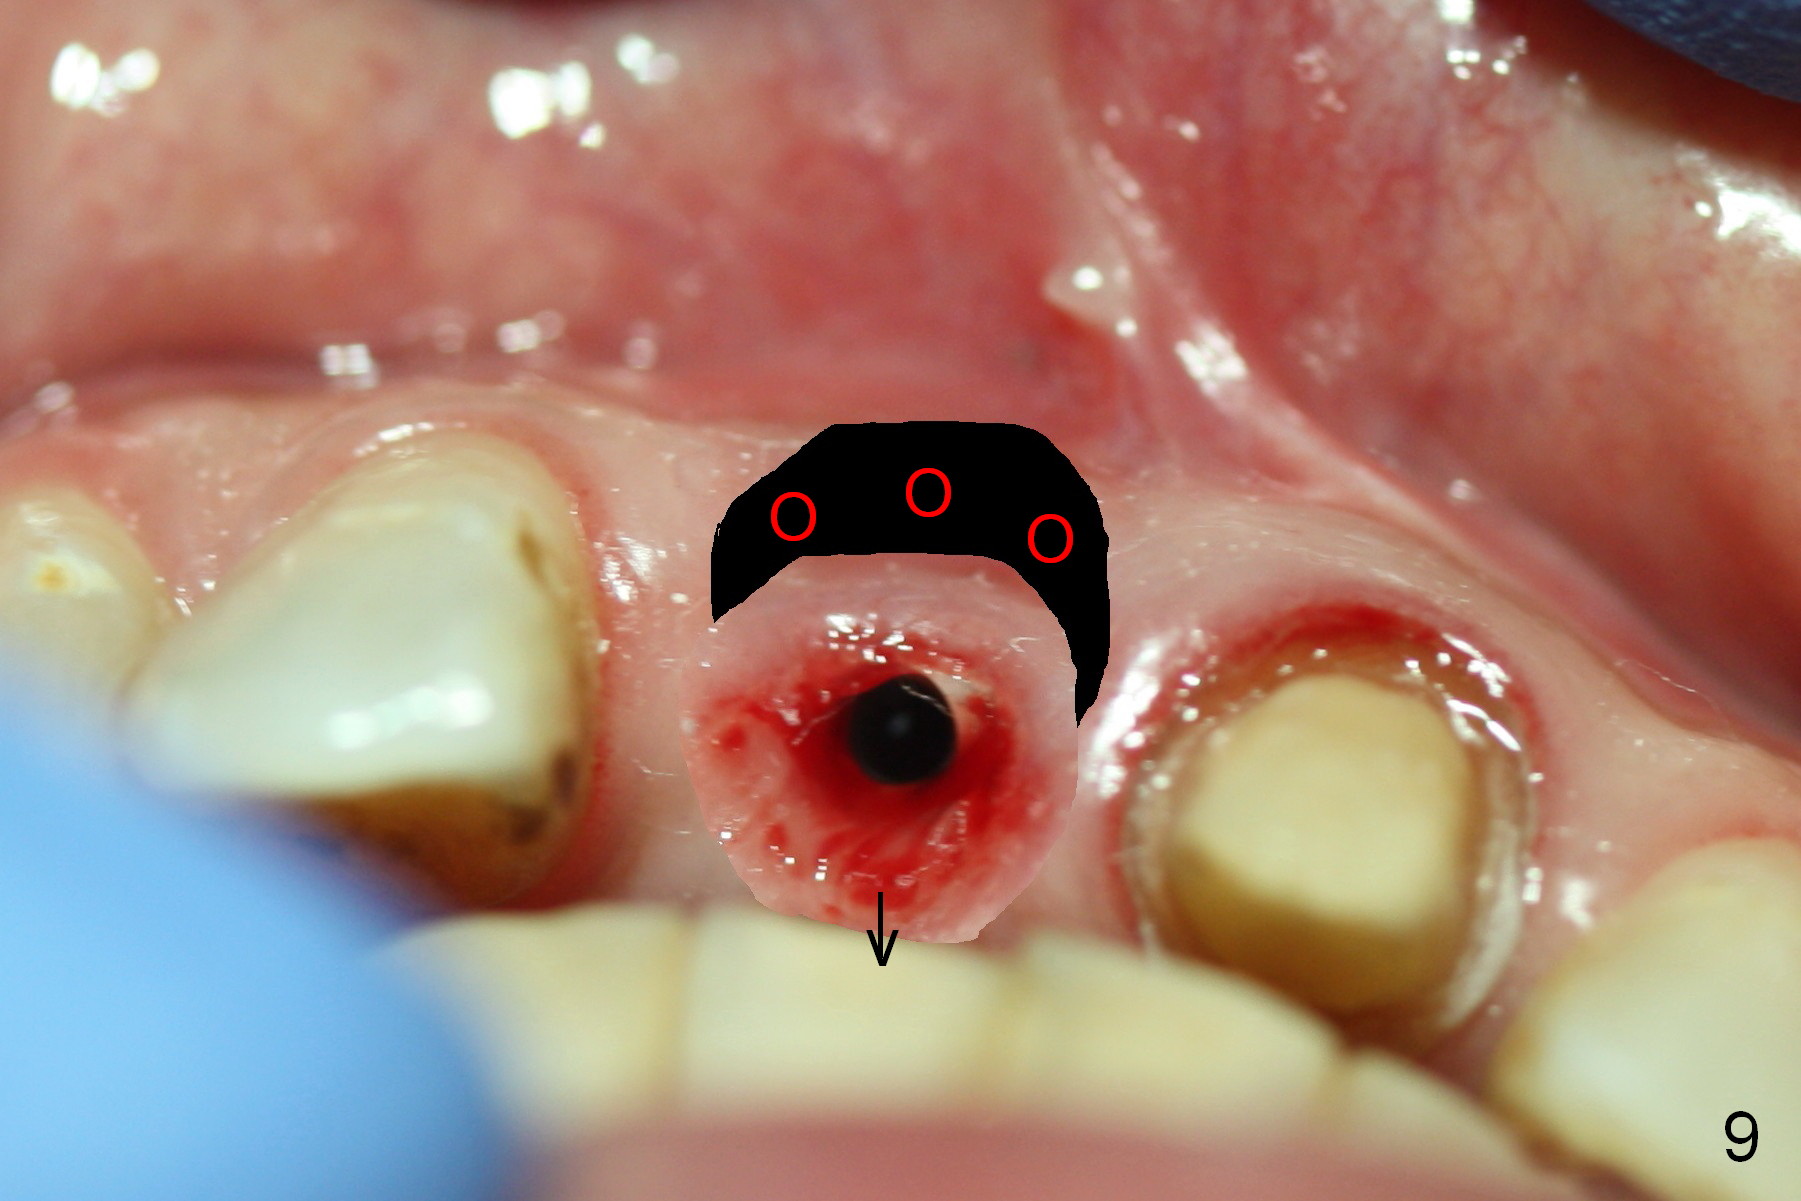

Fig.6,7 were taken a month ago when the Zirconium abutment was fractured, showing the position of the coronal end of the implant. To retrieve the abutment, an envelop incision will be made (Fig.8) with elevation of the buccal flap for the best visibility. Prepare abutment removing drivers (x3) and try in vitro. To improve cosmetics, the implant/bone segment seems to be required to be lingualized ~3 mm (Fig.9 arrow) with bone graft buccally (red circles, possibly chin graft).